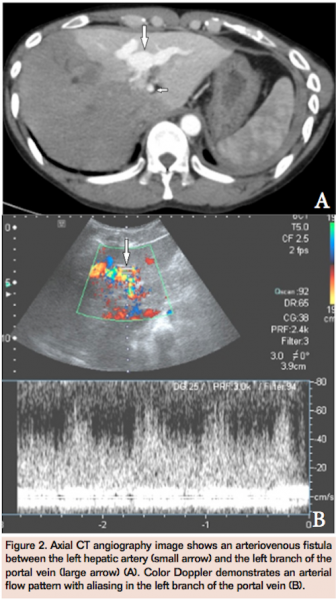

CT angiography (CTA) showed an aortic dissection, which extended from below the level of the superior mesenteric artery to the aortic bifurcation (Figures 1A and 1B). A 16 mm x 18 mm pseudoaneurysm was seen arising from a branch of the right hepatic artery (Figure 1C). There was also an arteriovenous fistula between the left hepatic artery and the left branch of the portal vein (Figures 2A and 2B). A loculated pleural effusion was seen along the posterior aspect of the left chest wall and within the major fissure. Multiple large subpleural bullae were present in both lungs. The coexistence of multiple unusual vascular complications and subpleural bullae in the lungs raised the possibility of a connective tissue disorder. Further physical examination revealed a high arched palate, clubbing, and an increased arm span:height ratio (168:163). There was no hypermobility of joints or hyperextensibility of skin. Serum markers for vasculitis were negative. The possibility of vascular Ehler-Danlos syndrome (VEDS) was considered.